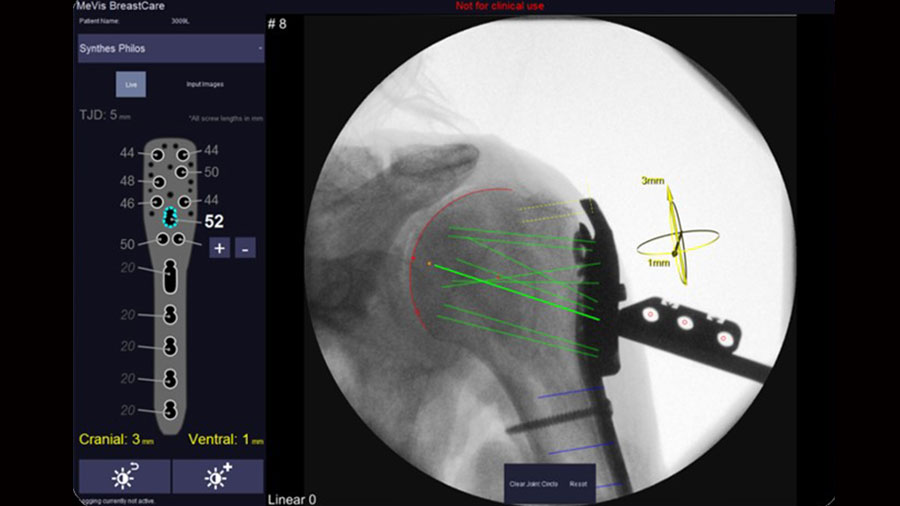

X-in-One: Placing implants safe and sound

The task of placing implants plays a key role in trauma and orthopedics surgery. Current solutions for computer aided surgery lack of wider acceptance due to considerable disadvantages regarding complexity, costs, and effectiveness.

Proposed solution

A simplified computer aided surgery system X-in-One has been developed* utilizing a conventional C-arm as imaging and navigation means rendering additional tracking and imaging equipment obsolete. The system provides simple integration into standard clinical routine and strong potential for improving clinical practice for a variety of surgical interventions in trauma and orthopedics.

*Graphical User Interface in collaboration with Mevis Medical AG